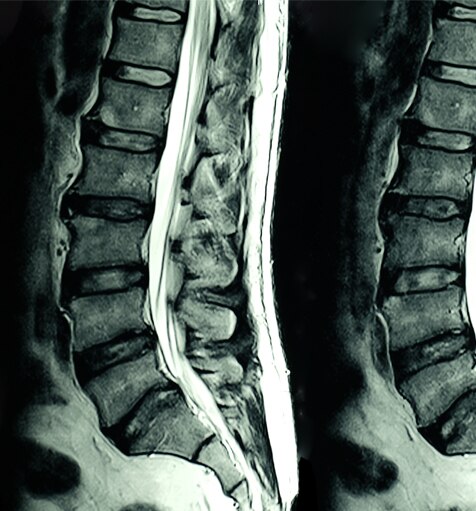

MRI (Magnetic Resonance Imaging) is a non-invasive scanning technology that produces cross sectional images of the body. It is used in a range of medical fields including: musculoskeletal, gastrointestinal, oncology, cardiovascular and neuroimaging. MRI scanning can differentiate soft tissue structures in any plane making it an invaluable diagnostic tool.

MRI scanners generate a strong magnetic field that is used in conjunction with radiofrequency currents to stimulate specific molecules in the body.

The behaviour of the molecules can be used to generate a three-dimensional image of body tissues. Example MRI images are shown below: